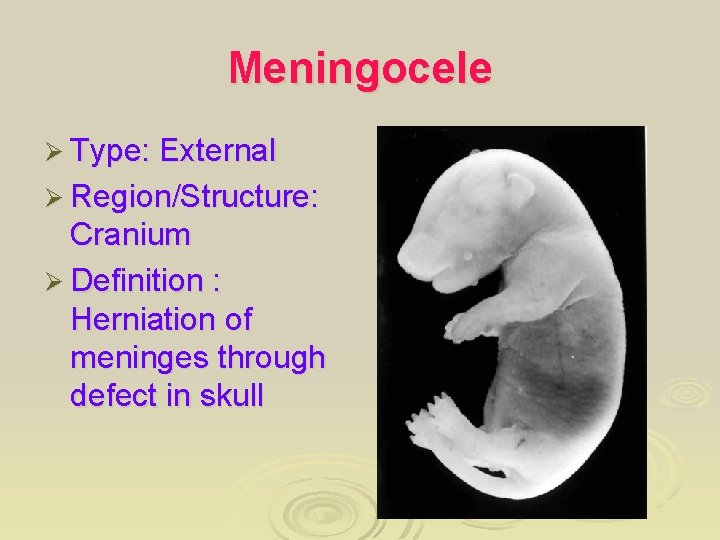

Meningocele Ø Type: External Ø Region/Structure: Cranium Ø Definition : Herniation of meninges through defect in skull